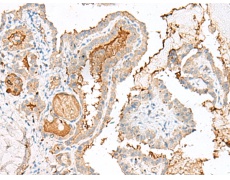

IHC positive control: |

Human colorectal cancer and Human thyroid cancer |

IHC Recommend dilution: |

40-200 |